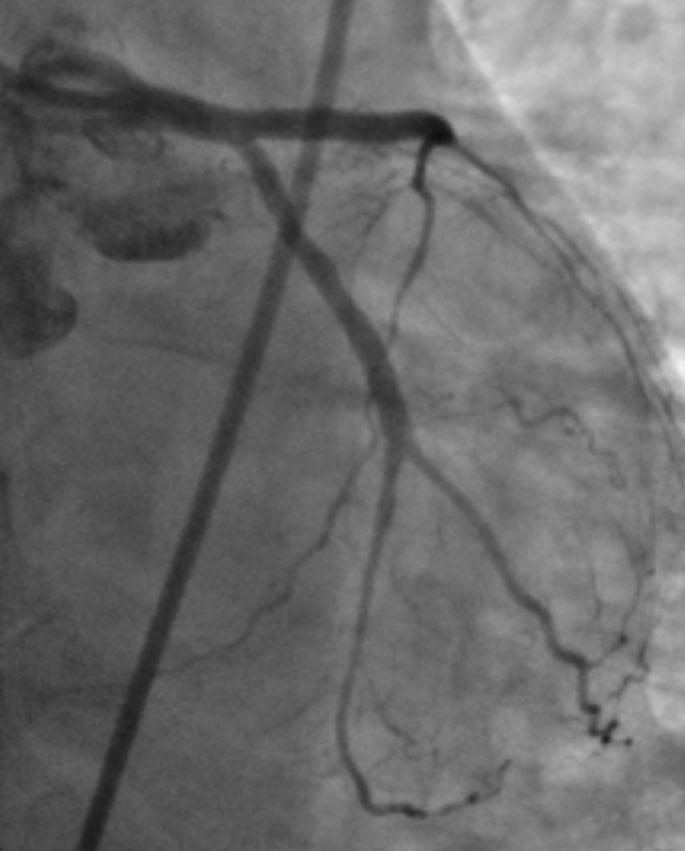

38m cp 30 hrs nstemi #RadialFirst opened LAD, brought back 2 weeks 7f guide #safefemoral #protectedpci #impella #ivus 4.5 DES in LAD>LM. Pot 5.0 #preclose home next day EF now 50

istentem's tweet image. 38m cp 30 hrs nstemi #RadialFirst opened LAD, brought back 2 weeks 7f guide #safefemoral #protectedpci #impella #ivus 4.5 DES in LAD>LM. Pot 5.0 #preclose home next day EF now 50